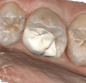

Desenho Digital Coroa Parcial e Total

Coroa Parcial e Total prontas para impressao 3D

Instalação em boca

Coroas impressas e ajustadas no modelo